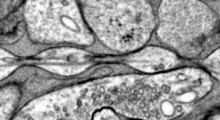

Il nuovo microscopio Firefly è ottimizzato per eseguire studi optogenetici esaminando molti neuroni contemporaneamente. Ogni punto luminoso qui rappresenta un neurone di un topo geneticamente modificato.Un microscopio appena sviluppato sta fornendo agli scienziati uno strumento notevolmente migliorato per studiare come i disturbi neurologici come l'epilessia e l'Alzheimer influenzano la comunicazione neuronale.

Il nuovo microscopio Firefly è ottimizzato per eseguire studi optogenetici esaminando molti neuroni contemporaneamente. Ogni punto luminoso qui rappresenta un neurone di un topo geneticamente modificato.Un microscopio appena sviluppato sta fornendo agli scienziati uno strumento notevolmente migliorato per studiare come i disturbi neurologici come l'epilessia e l'Alzheimer influenzano la comunicazione neuronale.

Il nuovo microscopio, chiamato Firefly, può vedere un'area di 6 mm di diametro, oltre cento volte più grande del campo visivo della maggior parte dei microscopi usati per l'optogenetica. Piuttosto che studiare l'attività elettrica di un neurone, l'ampia area di scansione rende possibile individuare gli impulsi elettrici che i neuroni usano per comunicare e poi osservare quegli impulsi che viaggiano da una cellula all'altra attraverso un grande circuito neurale contenente centinaia di cellule.

Nel cervello, ogni neurone si connette di solito ad altri mille neuroni, quindi la visualizzazione di una rete più grande è importante per capire come le malattie neurologiche influenzano la comunicazione neuronale.

I ricercatori hanno mostrato il loro nuovo microscopio usandolo per stimolare otticamente e registrare la fluorescenza dai neuroni umani in coltura. "I neuroni erano una grande confusione di spaghetti", ha detto Cohen. "Abbiamo dimostrato che è possibile risolvere 85 singoli neuroni contemporaneamente in una misurazione che richiede circa 30 secondi".

L'ampio campo visivo del microscopio e la capacità di visualizzazione veloce consentono di vedere i segnali elettrici che viaggiano rapidamente da neurone a neurone. L'osservazione della rete neuronale così grande è importante per capire come le malattie neurologiche influenzano la comunicazione neuronale.